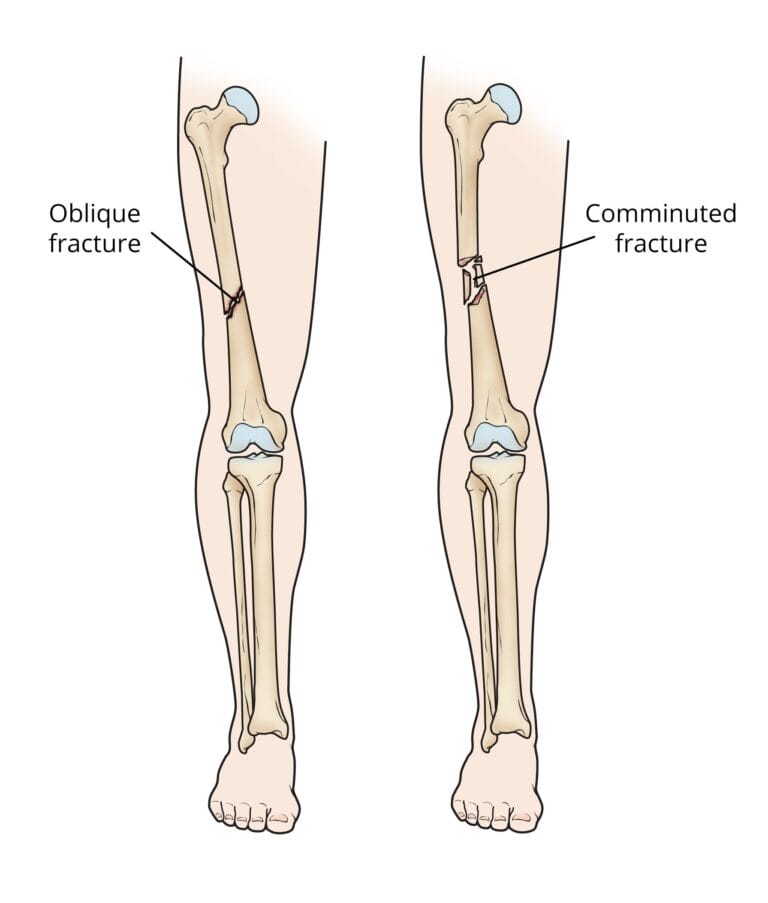

- Oblique fracture: Defined by an angled line running through the shaft.

- Comminuted fracture: The bone is broken into three or more fragments.

(Left) An oblique fracture has an angled line across the shaft. (Right) A comminuted fracture is broken into three or more pieces.